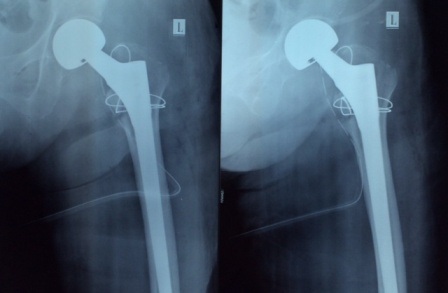

Sau khi hội chẩn, bệnh viện quyết định thực hiện phẫu thuật thay khớp háng cứu người bệnh. Trước cơ địa của một bệnh nhân lớn tuổi với nhiều bệnh lý về tim mạch, tiểu đường, huyết áp… rất nhiều nguy cơ có thể xảy ra trong cuộc mổ. Nhưng sau một giờ khẩn trương, ê kíp phẫu thuật đã kiểm soát tốt các chỉ số sinh tồn, thay thành công khớp háng bán phần cho bà cụ.